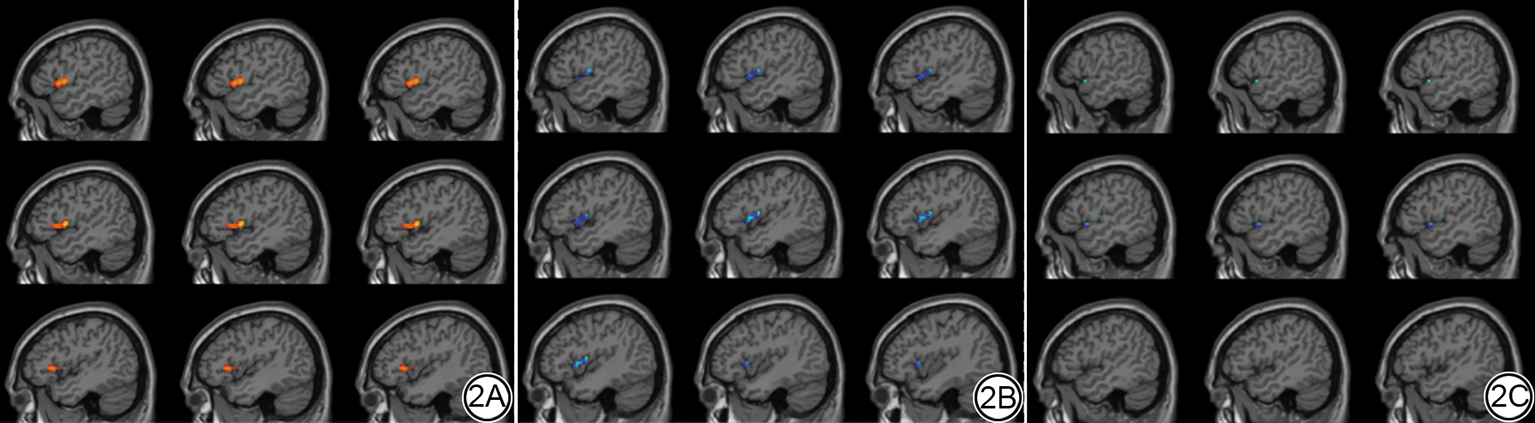

基于ICA提取的空间图(Z值)比较结果显示,与HC组相比,PMS组SN内左侧额下回、岛叶以及颞下回的FC升高(FDR校正,P<0.05,见表3图2A),右侧ECN、左侧ECN、腹侧DMN及背侧DMN未见显著变化。且2 Hz-taVNS和25 Hz-taVNS均可显著改变PMS患者SN内的FC,2 Hz主要下调左侧前额叶、左侧额下回、岛叶及颞上回FC(FDR校正,P<0.05,详见表4图2B)。25 Hz主要下调左侧颞上回FC(FDR校正,P<0.05,详见表4图2C)。HC组在2 Hz-taVNS和25 Hz-taVNS刺激时均无显著调节效应。此外,PMS组与HC组在st-taVNS刺激时SN内部均未表现出显著的FC变化。

图2  PMS患者SN内部异常FC以及不同频率taVNS对PMS患者异常FC的即时效应。2A:PMS患者较HC显著差异的脑区,暖色调表示PMS患者较于HC组FC显著增强的脑区;2B、2C分别是2 Hz和25 Hz-taVNS所引起的即时调节变化,冷色调表示taVNS后FC显著降低的脑区。PMS:经前期综合征;SN:突显网络;FC:功能连接;taVNS:经皮耳迷走神经刺激;HC:健康对照。

Fig. 2  Abnormal FC within the SN in PMS patients compared to HC and immediate effects of different taVNS frequencies in PMS patients. 2A: Brain regions showing significant FC differences between PMS patients and HC; warm colors indicate regions with significantly increased FC in PMS compared to HC. 2B-2C: Immediate modulation effects induced by 2 Hz and 25 Hz taVNS, respectively; cool colors represent brain regions with significantly decreased FC after stimulation. Red dots represent HC; blue dots represent PMS. PMS: premenstrual syndrome; SN: salience network; FC: functional connectivity; taVNS: transcutaneous auricular vagus nerve stimulation; HC: healthy controls.